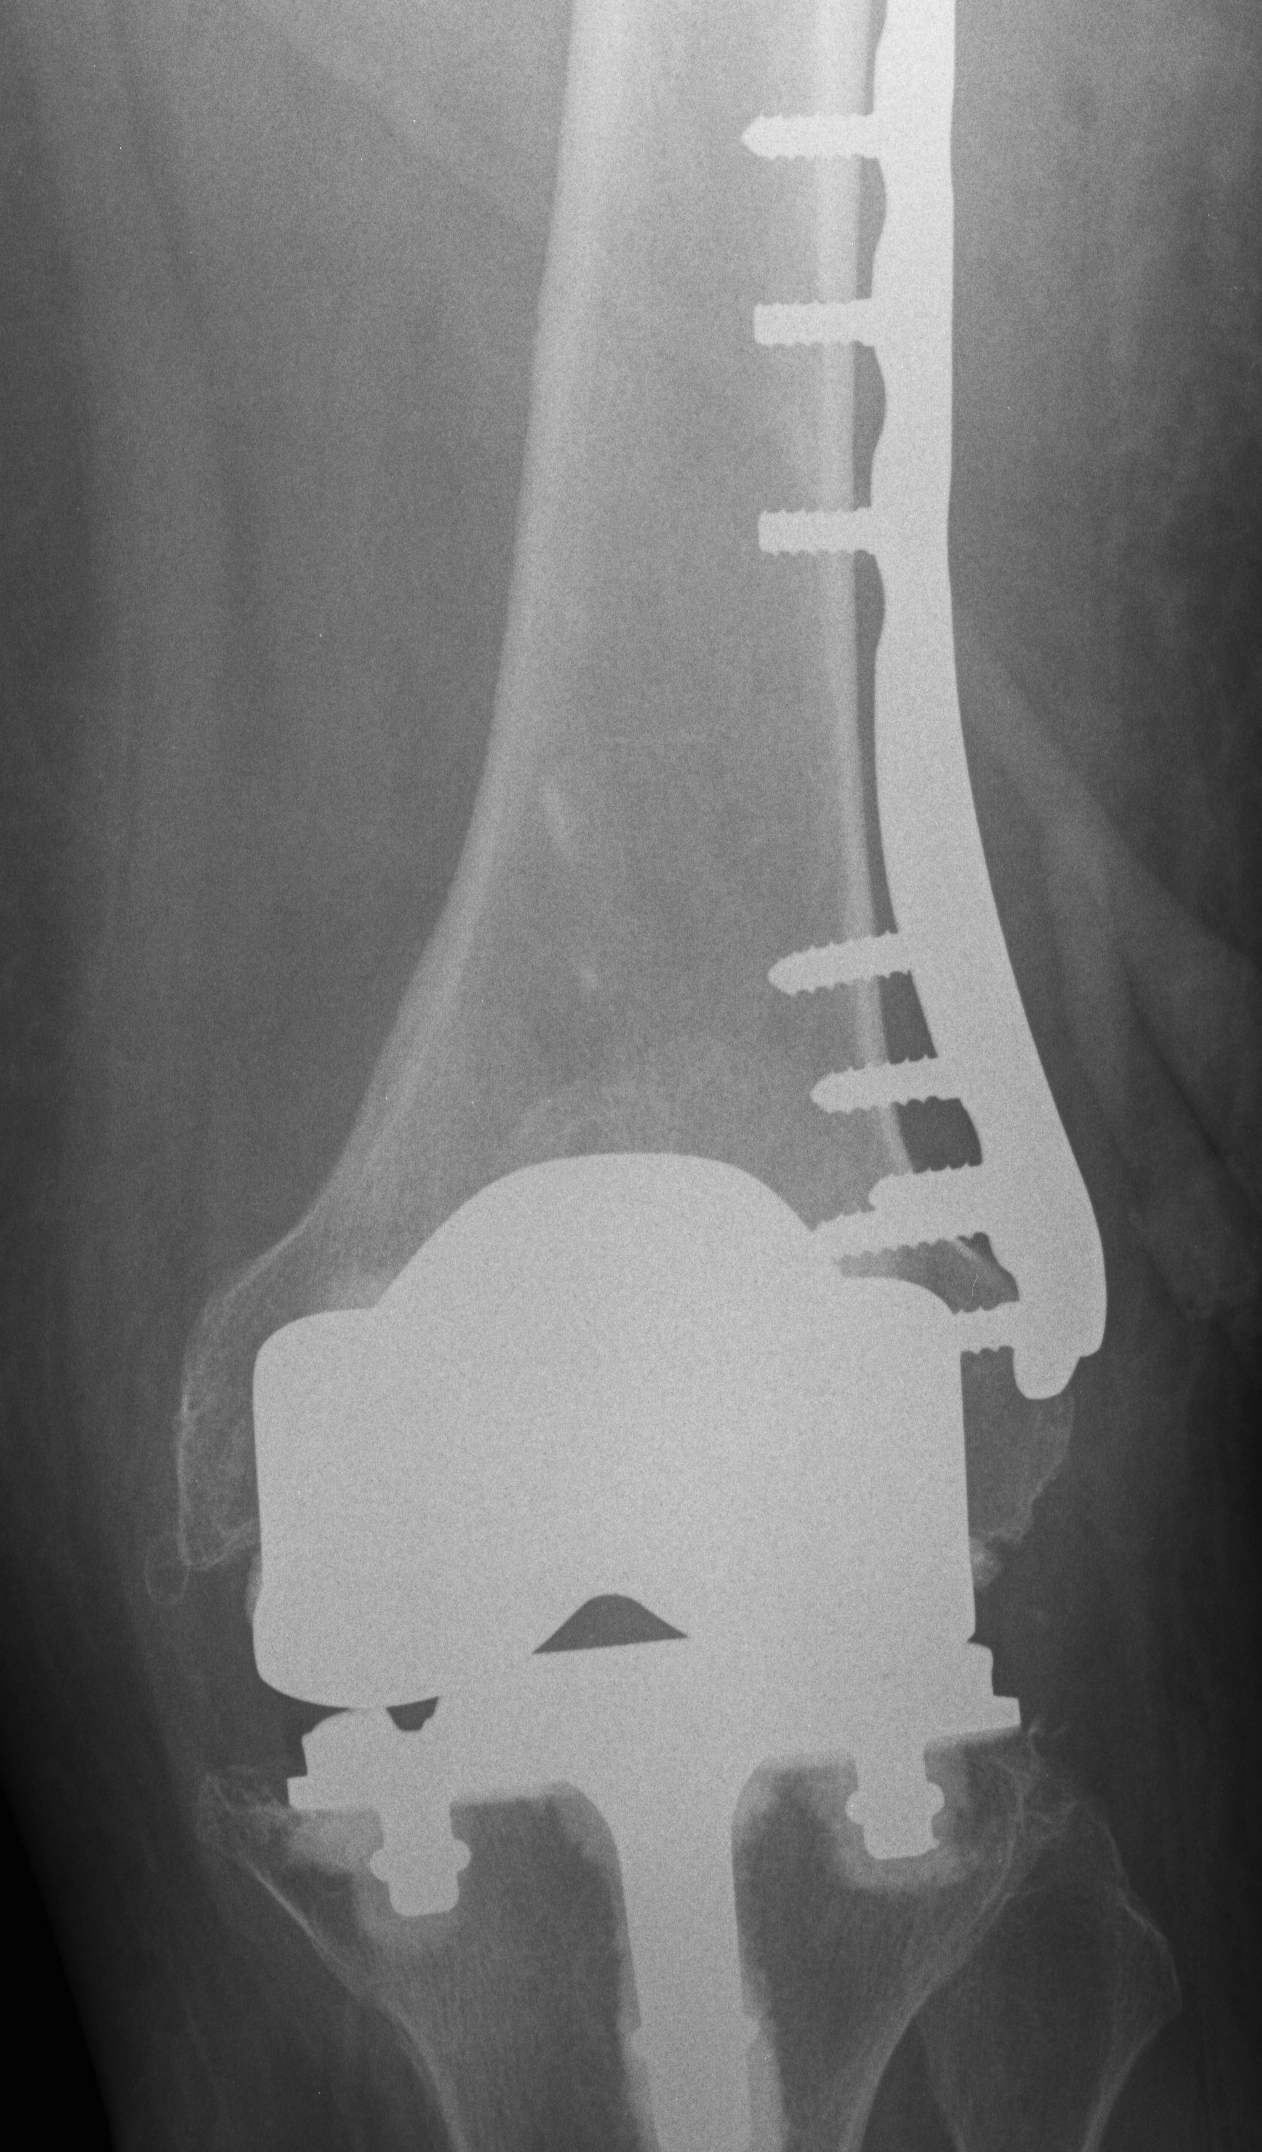

1.  Lateral locking plate

TKR Periprosthetic Fracture Minimall Dislplaced CTTKR Periprosthetic Fracture Locking Plate APTKR Periprosthetic Fracture Locking Plate Lateral

Technique

Minimally invasive technique

- may need unicortical screws distally